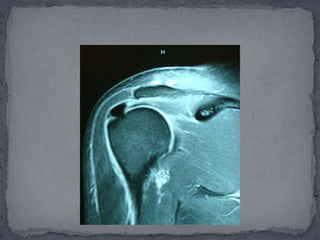

Las imágenes de resonancia magnética permiten una completa evaluación del hombro. Con esta modalidad de imágenes, es ahora posible diagnosticar enfermedad del manguito, desde una simple tendinosis hasta una ruptura completa, así como rupturas intratendinosas o rupturas en el aspecto bursal del tendón.Las imágenes de resonancia magnética han demostrado 100% de sensibilidad y 95% de especificidad en el diagnóstico de rupturas completas, y predice consistentemente el tamaño del desgarro del tendón. La atrofia del músculo supraespinatus se correlaciona con el tamaño de unacompleta y crónica ruptura del tendón. La sensibilidad y especificidad en la diferenciación de tendinitis de la degeneración del tendón en un 82 a 85% y la diferenciación de un tendón normal de uno afectado por tendinitis con signos de pinzamiento con sensibilidad y 80 especificidad del 93% y 87% respectivamente.

Las imágenes deresonancia magnética permiten una completa evaluación del hombro. Con esta modalidad de imágenes, es ahora posible diagnosticar enfermedad del manguito, desde una simple tendinosis hasta una ruptura completa, así como rupturas intratendinosas o rupturas en el aspecto bursal del tendón.Las imágenes de resonancia magnética han demostrado 100% de sensibilidad y 95% de especificidad en el diagnóstico de rupturas completas, y predice consistentemente el tamaño del desgarro del tendón. La atrofia del músculo supraespinatus se correlaciona con el tamaño de unacompleta y crónica ruptura del tendón. La sensibilidad y especificidad en la diferenciación de tendinitis de la degeneración del tendón en un 82 a 85% y la diferenciación de un tendón normal de uno afectado por tendinitis con signos de pinzamiento con sensibilidad y 80 especificidad del 93% y 87% respectivamente.